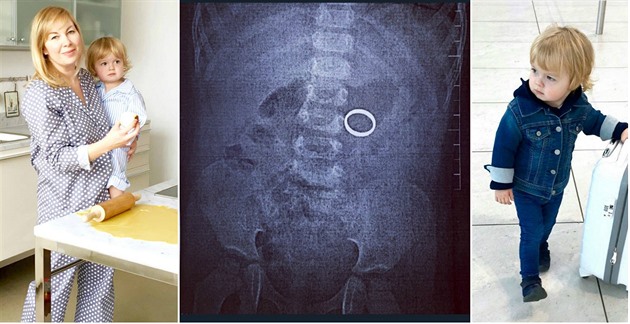

V rodině televizní kuchařky Dity P. bylo před několika dny pořádně rušno. Teprve dvouletý syn totiž využil chvilku nepozornosti své maminky a spolkl snubní prsten, který si před vařením položila na kuchyňskou linku.

Pecháčková tak prožívala těžké chvíle a hlavou se jí honily ty nejčernější myšlenky. Všechno ale nakonec dopadlo dobře. Se synem zašla k lékaři a ten ji doporučil vyčkat, až prsten doputuje do konečníku. „Měla jsem velký strach, ale všechno dobře dopadlo. Počkali jsme a prstýnek je venku. Neptejte se mě na detaily, asi to každému dojde,“ řekla serveru Blesk.cz kuchařka.

Nyní si na drobné věci v bytě dává pozor. Podobnou situaci by si totiž velmi nerada zopakovala, přestože to nyní bere celé s nadhledem.